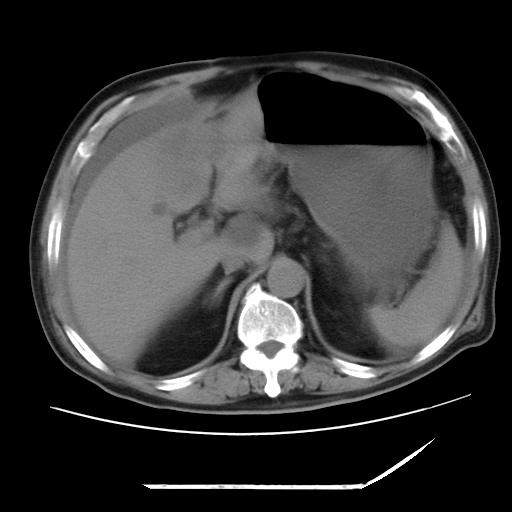

以下是引用zxl51642在2009-8-12 18:55:00的发言:[br]1、肠系膜脂肪浑浊,密度增高,腹水,支持腹膜炎诊断;2、右肾盂及输尿管中段结石,左输尿管起始段结石;3、胆囊切除术后改变?4、双侧胸膜腔少量积液;5、胰腺体积不大,勾勒清楚,肾前筋膜无增厚,不支持胰腺炎,请结合血尿淀粉酶及临床。